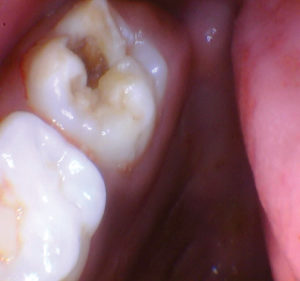

Caso 2

Un nuevo paciente de 7 años presentó una importante descomposición e hipocalcificación en el primer molar permanente superior derecho. Durante mucho tiempo se ha demostrado que los primeros molares permanentes cariados e hipocalcificados en pacientes pediátricos le dan al profesional un dilema restaurador difícil. ¿Deberíamos intentar prepararnos y restaurarlos conservadoramente? ¿Deberíamos ser más agresivos y restaurar con una cobertura completa como una corona de acero inoxidable bien adaptada? Activa proporciona una gran alternativa en estos casos, con liberación de calcio, fosfato y fluoruro junto con alta resistencia y resistencia a la fractura.

Figura 1. Después del ataque ácido y el uso del agente de unión Scotchbond Universal (3M), los dos molares primarios superiores se restauraron con Activa Bioactive Restorative A2. |

Figura 2. Una vez que se excavó la descomposición y se colocaron los márgenes en superficies sólidas, se colocó un bisel pesado en el esmalte para aumentar la resistencia de la unión y la integridad marginal. El área oscura central era sólida. El diente estaba revestido con una base / revestimiento Activa. |